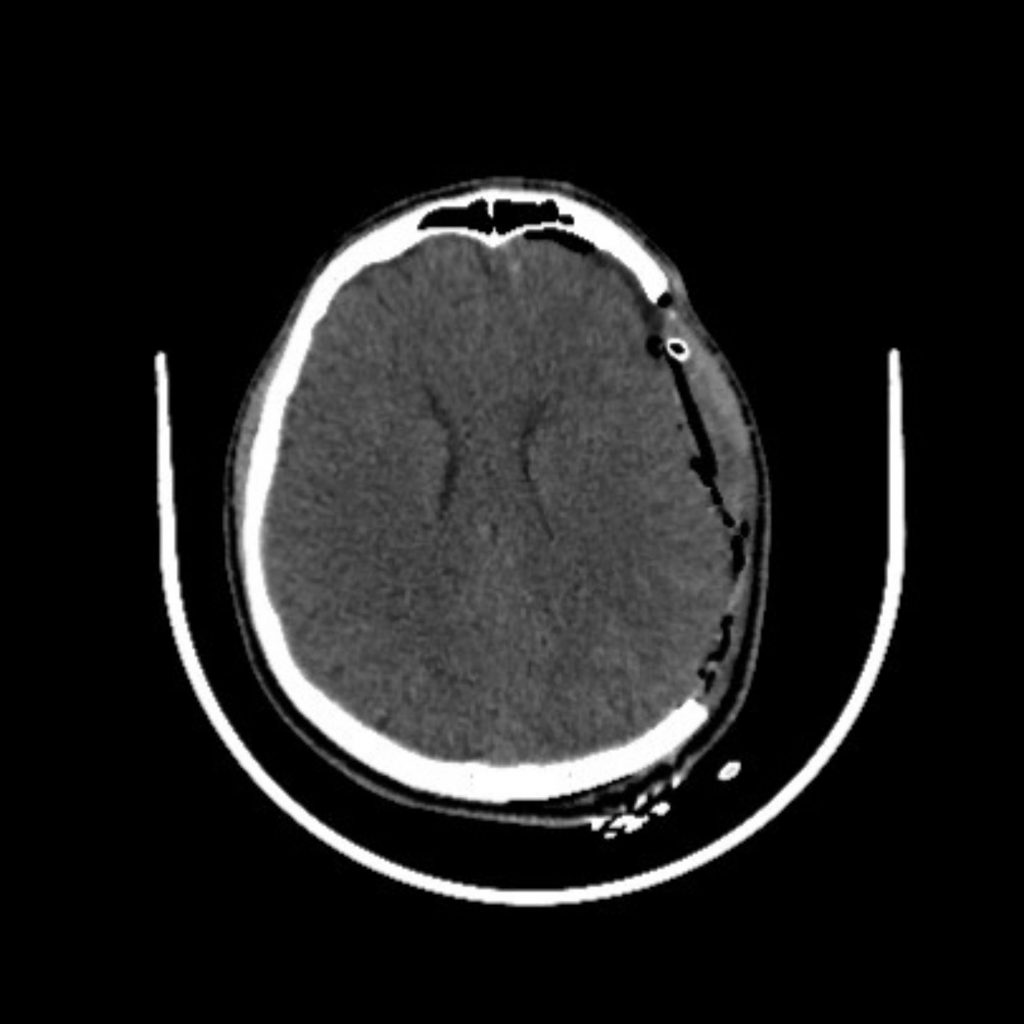

Hình ảnh cận lâm sàng sau phẫu thuật

Trước tình trạng nguy kịch, người bệnh được chỉ định phẫu thuật cấp cứu để lấy máu tụ ngoài màng cứng. Các bác sĩ tiến hành mở sọ, lấy trọn khối máu tụ và nhanh chóng kiểm soát nguồn chảy máu. Đây là nhánh động mạch lớn của màng não, nên việc cầm máu kịp thời đóng vai trò then chốt, giúp ngăn khối máu tụ tiếp tục phát triển, giảm thời gian chèn ép não và hạn chế tối đa nguy cơ di chứng nặng nề sau phẫu thuật như yếu liệt nửa người.